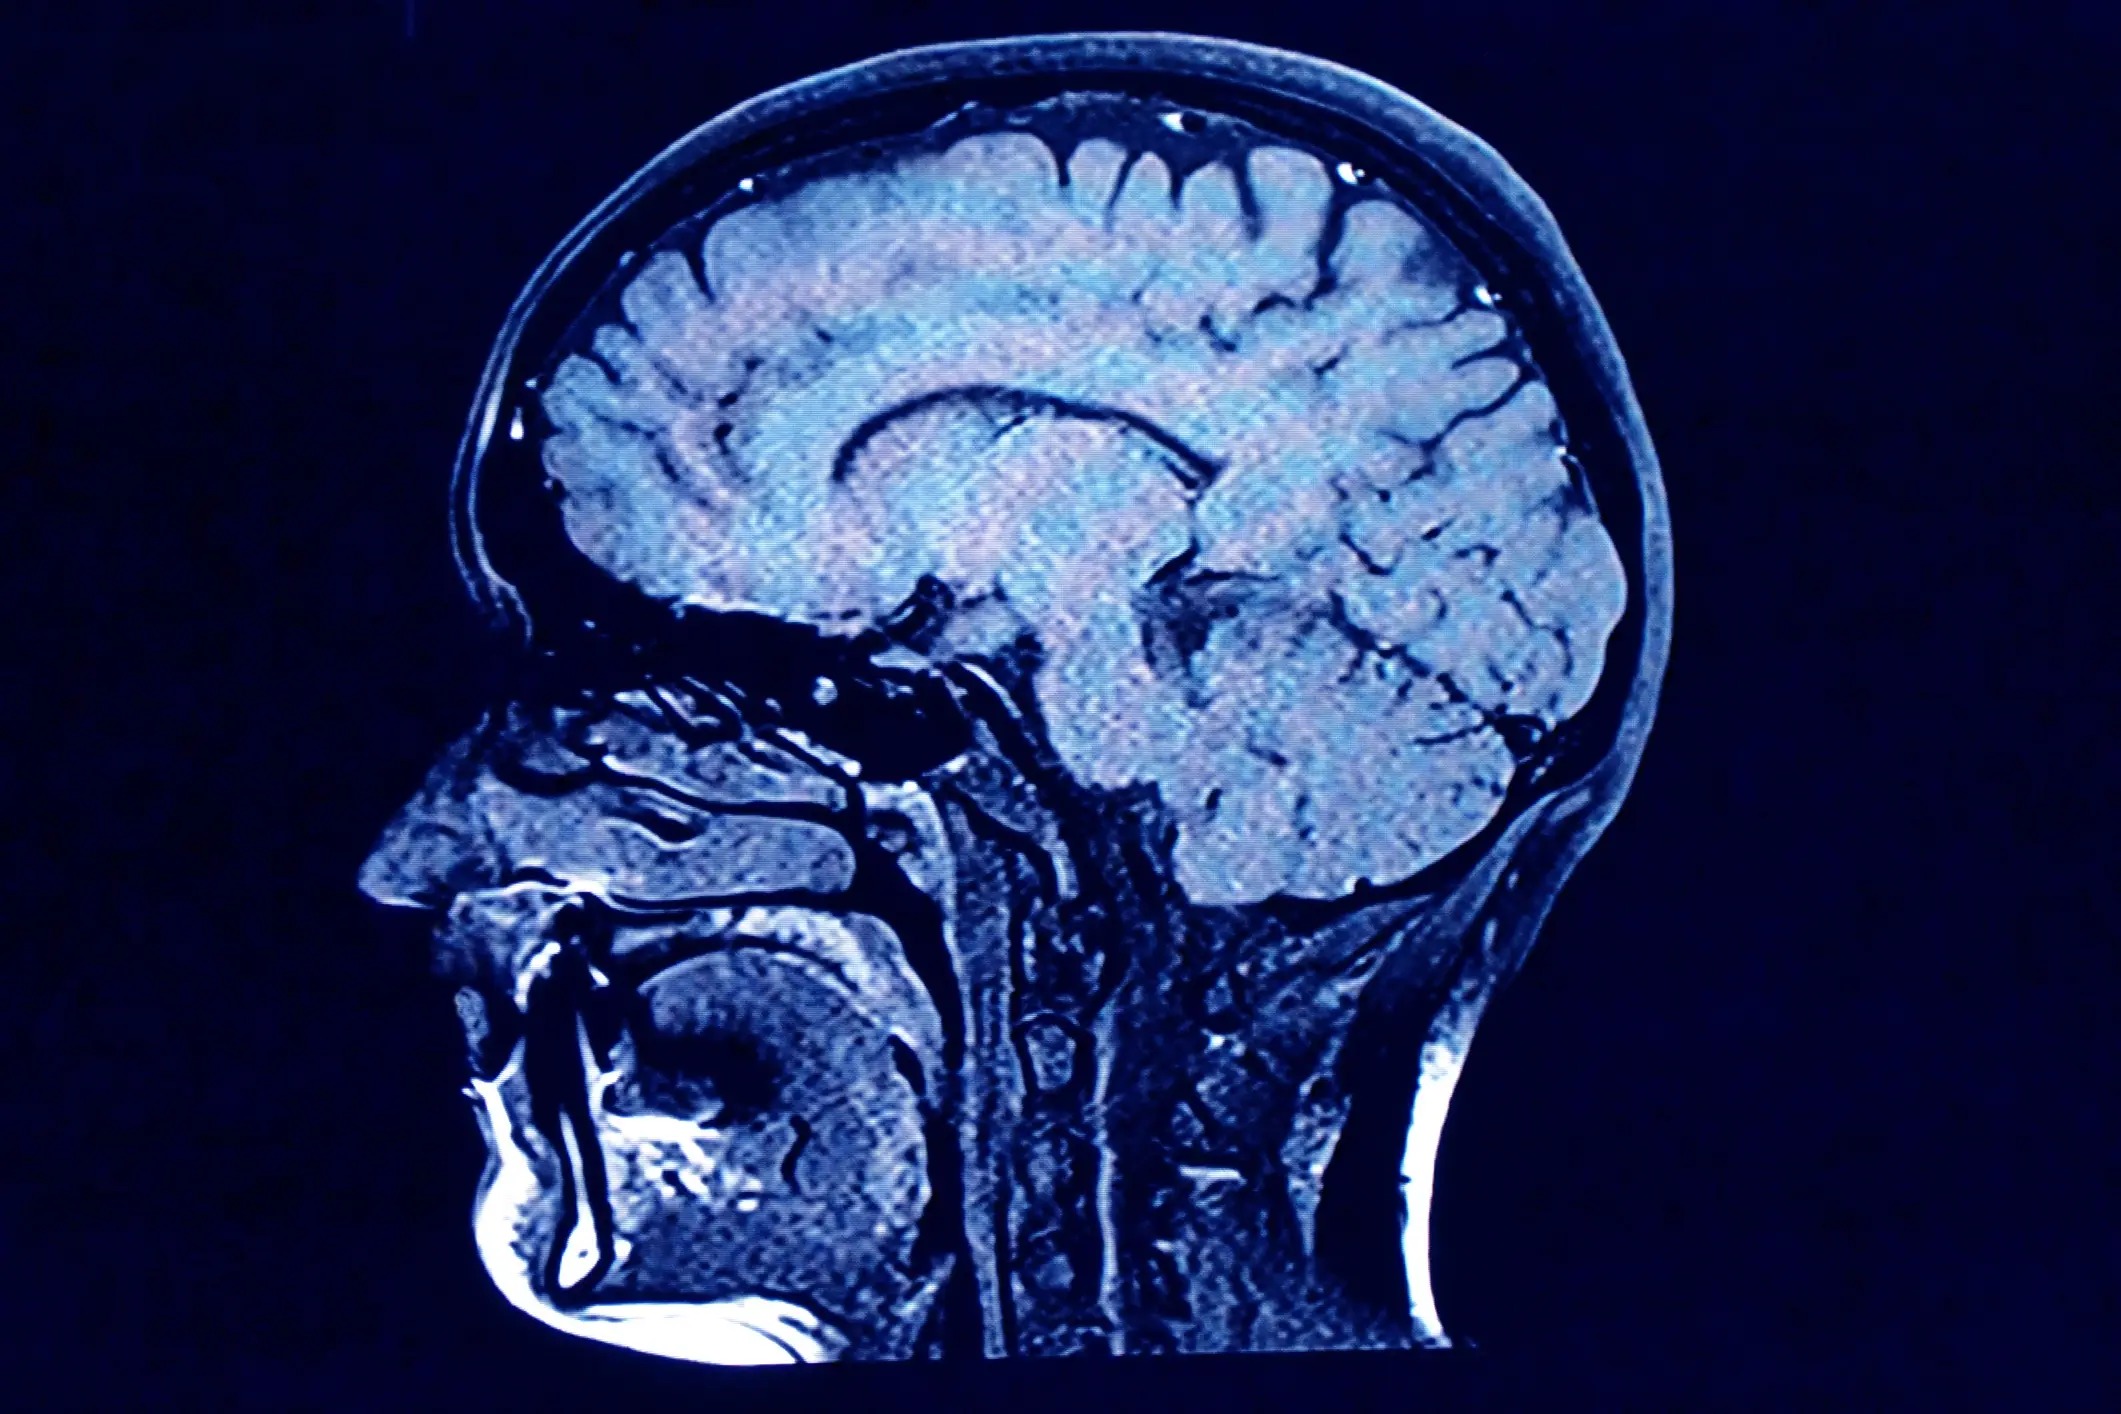

People have been left stunned after watching a jaw-dropping simulation of what happens to our brains within 10 minutes of dying.

But did you know some reputable studies claim brain activity can continue for up to several minutes after death?

Research undertaken by New York’s Stony Brook University of Medicine discovered that our brains come to a standstill so ‘slowly’ that it could take ‘hours’ for them to come to a complete standstill.

Elsewhere, Dr Sam Parnia - the director of critical care and resuscitation research at NYU Langone School of Medicine in New York City - and his team found that bursts of brain activity took place in four people after their hearts stopped.

Speaking about the study, published in the Proceedings of the National Academy of Sciences, Parnia told Live Science that even after our breathing and heartbeat stop, we remain conscious for around two to 20 seconds.

It’s understood that’s how long the cerebral cortex can survive without oxygen.

Once the ‘thinking’ part of the brain flatlines after 20 seconds, no brainwaves will be visible on the electric monitor.

This will eventually result in the death of brain cells hours after the heart has stopped.